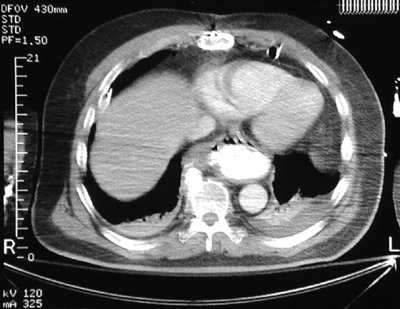

| In this chest CT scan there is dilation of the lower esophagus merging into the upper gastric fundus, filled with bright contrast, representing a hiatal hernia. This condition may be associated with gastroesophageal reflux. The diaphragmatic hiatus is large enough for a portion of stomach to "slide" through the larger opening. |